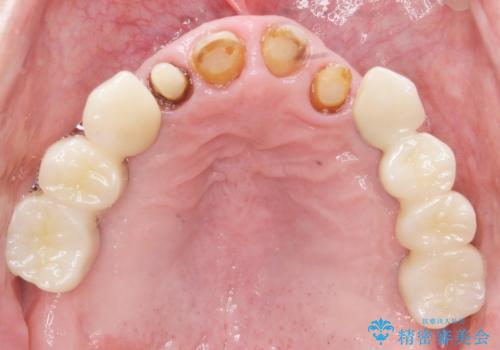

古い被せ物や土台・虫歯をしっかり除去したのち、セラミック治療を行いました。

患者様のご希望により、根尖病変の明らかな左上2のみ根管治療を行いました。

- ¥610,000 (根管治療×1本、土台×4本、仮歯×4本、クラウン×4本)費用は治療当時の料金となります